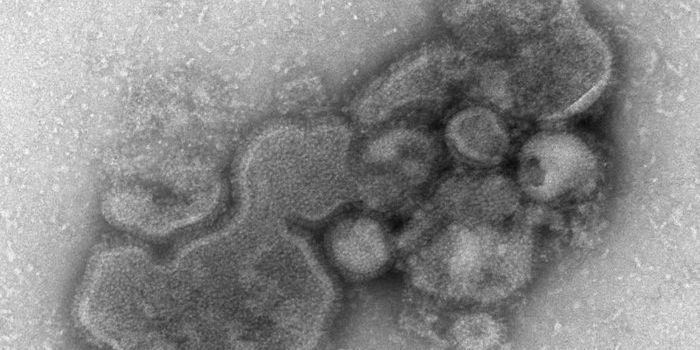

JUL 05, 2022ImmunologyResearchers have created a new 'universal' flu vaccine, which is directed against type A influenza viruses. It w ...

JUN 01, 2021ImmunologySeasonal flu vaccines only work around 40 to 60 percent of the time, says the U.S. Centers for Disease Control and Preve ...

NOV 17, 2021MicrobiologyEvery year, there is a flu outbreak, and the severity can depend on many factors, like what strain is circulating. Last ...

OCT 17, 2017ImmunologyThe influenza vaccine may not be as effective as it needs to be for young leukemia patients, who are at an especially hi ...